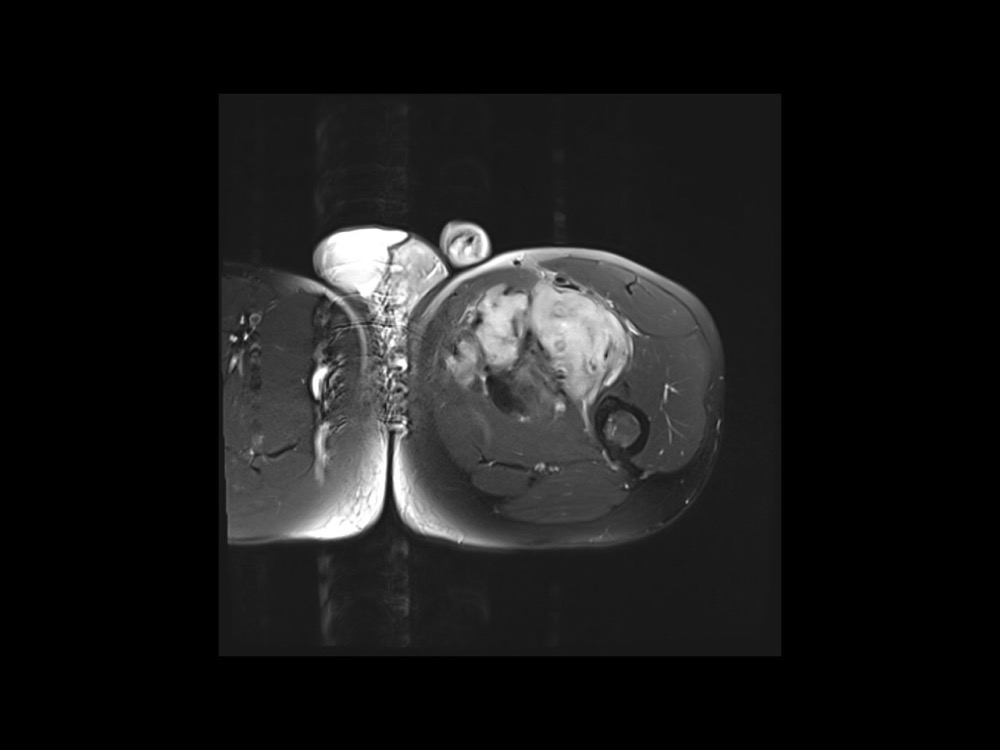

Moalla / Mihoubi-Bouvier / Drapé 18/05/2022